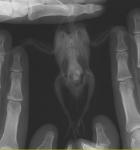

Сегодня, сдала анализ на бактериальный посев волнистику и розелле. Через неделю будут готовы результаты. И сделала рентген волнистику, выкладываю снимки

post-21892-1290988329_thumb.jpg post-21892-1290988344_thumb.jpg

Я делала рентген в Шанс Био на Цветном бульваре. Записали диск с программой, как и ранее. Если плохо видно, то я могу выслать на почту программу со снимками.

Lyalka, на рентгене все еще видно затемнение на суставе, хоть оно и стало заметно меньше. Или, возможно, воспаление практиески прошло, а теперь заново начинается.

Стоит повторить компрессы, предложенные Тимериным.

Крупно:

___1.JPG ___2.JPG